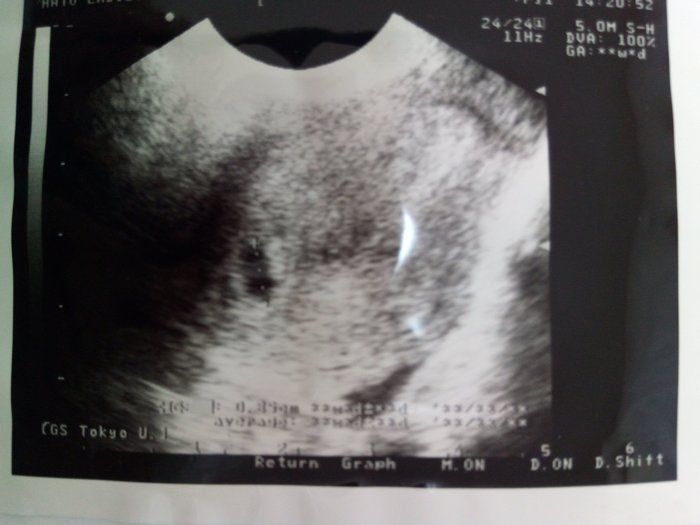

Tomomiさんの妊娠6週目のエコー写真 4日で3.9mmも成長!!

心拍確認から数日後、腰痛と少量の出血が起こり、急遽クリニックへ。「お願い…なんとかしがみついていてね…」と、祈る気持ちで診察を受けましたが、ベビちゃんは無事でした。たった数日での急成長に不安も吹き飛びました。

赤ちゃんがママから栄養をもらう“ホワイトリング”も見え、まさに天使のようでした(笑)。